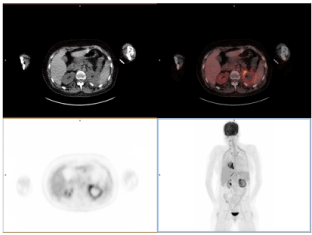

24-yr-old female, with history of diabetes and diagnosed of grey zone lymphoma (DLCBL/HL), underwent allogeneic stem cell transplantation (SCT) in October 2017. About the day +100 after SCT, she was admitted to our center with fever and complaints of pain in the left flank. Atypical consolidation area in right inferior lung lobe was seen in chest CT (Figure 1A), so the patient underwent to an 18F-FDG PET/CT to discard relapse of lymphoma. 18F-FDG PET/CT study showed peripheral 18F-FDG uptake in the pulmonary lesion (Figure 1B). In addition, an ametabolic area in the left kidney was seen on transverse fused PET/CT and MIP images (Figures 1C and 1D) which corresponded with the pain location referred by the patient and was informed as a probable renal infarction.

Figure 1. A: Atypical consolidation area in right inferior lung lobe was seen in chest CT. B: 18F-FDG PET/CT study showed peripheral 18F-FDG uptake in the pulmonary. C and D: An ametabolic area in the left kidney was seen on transverse fused PET/CT and MIP images